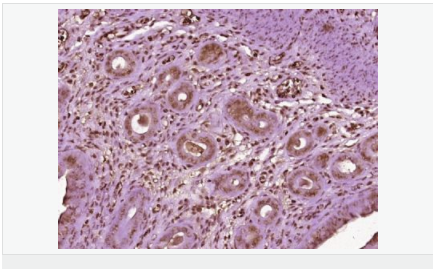

| 產(chǎn)品應用 | WB=1:500-2000 IHC-P=1:100-500 IHC-F=1:100-500 Flow-Cyt=1ug/Test ICC=1:100-500 IF=1:100-500 (石蠟切片需做抗原修復) not yet tested in other applications. optimal dilutions/concentrations should be determined by the end user. |

| 細胞定位 | 細胞核 細胞漿 |

| 產(chǎn)品介紹 | Estrogen and progesterone receptor are members of a family of transcription factors that are regulated by the binding of their cognate ligands. The interaction of hormone-bound estrogen receptors with estrogen responsive elements(EREs) alters transcription of ERE-containing genes. The carboxy terminal region of the estrgen receptor contains the ligand binding domain, the amino terminus serves as the transactivation domain, and the DNA binding domain is centrally located. Two forms of estrogen receptor have been identified, ER alpha and ER beta. ER alpha and ER beta have been shown to be differentially activated by various ligands. The biological response to progesterone is mediated by two distinct forms of the human progesterone receptor (hPR-Aand hPR-B), which arise from alternative splicing. In most cells, hPR-B functions as a transcriptional activator of progesterone-responsive gene, whereas hPR-A function as a transcriptional inhibitor of all steroid hormone receptors. Function: The steroid hormones and their receptors are involved in the regulation of eukaryotic gene expression and affect cellular proliferation and differentiation in target tissues. Progesterone receptor isoform B (PRB) is involved activation of c-SRC/MAPK signaling on hormone stimulation. Isoform A is inactive in stimulating c-Src/MAPK signaling on hormone stimulation. Subunit: Interacts with SMARD1 and UNC45A. Interacts with CUEDC2; the interaction promotes ubiquitination, decreases sumoylation, and repesses transcriptional activity. Interacts with PIAS3; the interaction promotes sumoylation of PR in a hormone-dependent manner, inhibits DNA-binding, and alters nuclear export. Interacts with SP1; the interaction requires ligand-induced phosphorylation on Ser-345 by ERK1/2 MAPK. Interacts with PRMT2. Subcellular Location: Nucleus. Cytoplasm. Note=Nucleoplasmic shuttling is both homone- and cell cycle-dependent. On hormone stimulation, retained in the cytoplasm in the G(1) and G(2)/M phases. Isoform A: Nucleus. Cytoplasm. Note=Mainly nuclear. Post-translational modifications: Phosphorylated on multiple serine sites. Several of these sites are hormone-dependent. Phosphorylation on Ser-294 occurs preferentially on isoform B, is highly hormone-dependent and modulates ubiquitination and sumoylation on Lys-388. Phosphorylation on Ser-102 and Ser-345 also requires induction by hormone. Basal phosphorylation on Ser-81, Ser-162, Ser-190 and Ser-400 is increased in response to progesterone and can be phosphorylated in vitro by the CDK2-A1 complex. Increased levels of phosphorylation on Ser-400 also in the presence of EGF, heregulin, IGF, PMA and FBS. Phosphorylation at this site by CDK2 is ligand-independent, and increases nuclear translocation and transcriptional activity. Phosphorylation at Ser-162 and Ser-294, but not at Ser-190, is impaired during the G(2)/M phase of the cell cycle. Phosphorylation on Ser-345 by ERK1/2 MAPK is required for interaction with SP1. Sumoylation is hormone-dependent and represses transcriptional activity. Sumoylation on all three sites is enhanced by PIAS3. Desumoylated by SENP1. Sumoylation on Lys-388, the main site of sumoylation, is repressed by ubiquitination on the same site, and modulated by phosphorylation at Ser-294. Similarity: Belongs to the nuclear hormone receptor family. NR3 subfamily. Contains 1 nuclear receptor DNA-binding domain. SWISS: P06401 Gene ID: 5241 Database links: Entrez Gene: 5241 Human Entrez Gene: 18667 Mouse Entrez Gene: 100009094 Rabbit Omim: 607311 Human SwissProt: P06401 Human SwissProt: Q00175 Mouse SwissProt: P06186 Rabbit Unigene: 2905 Human Unigene: 32405 Human Unigene: 742403 Human Unigene: 12798 Mouse Unigene: 437703 Mouse Unigene: 1947 Rabbit Unigene: 10303 Rat Important Note: This product as supplied is intended for research use only, not for use in human, therapeutic or diagnostic applications. |